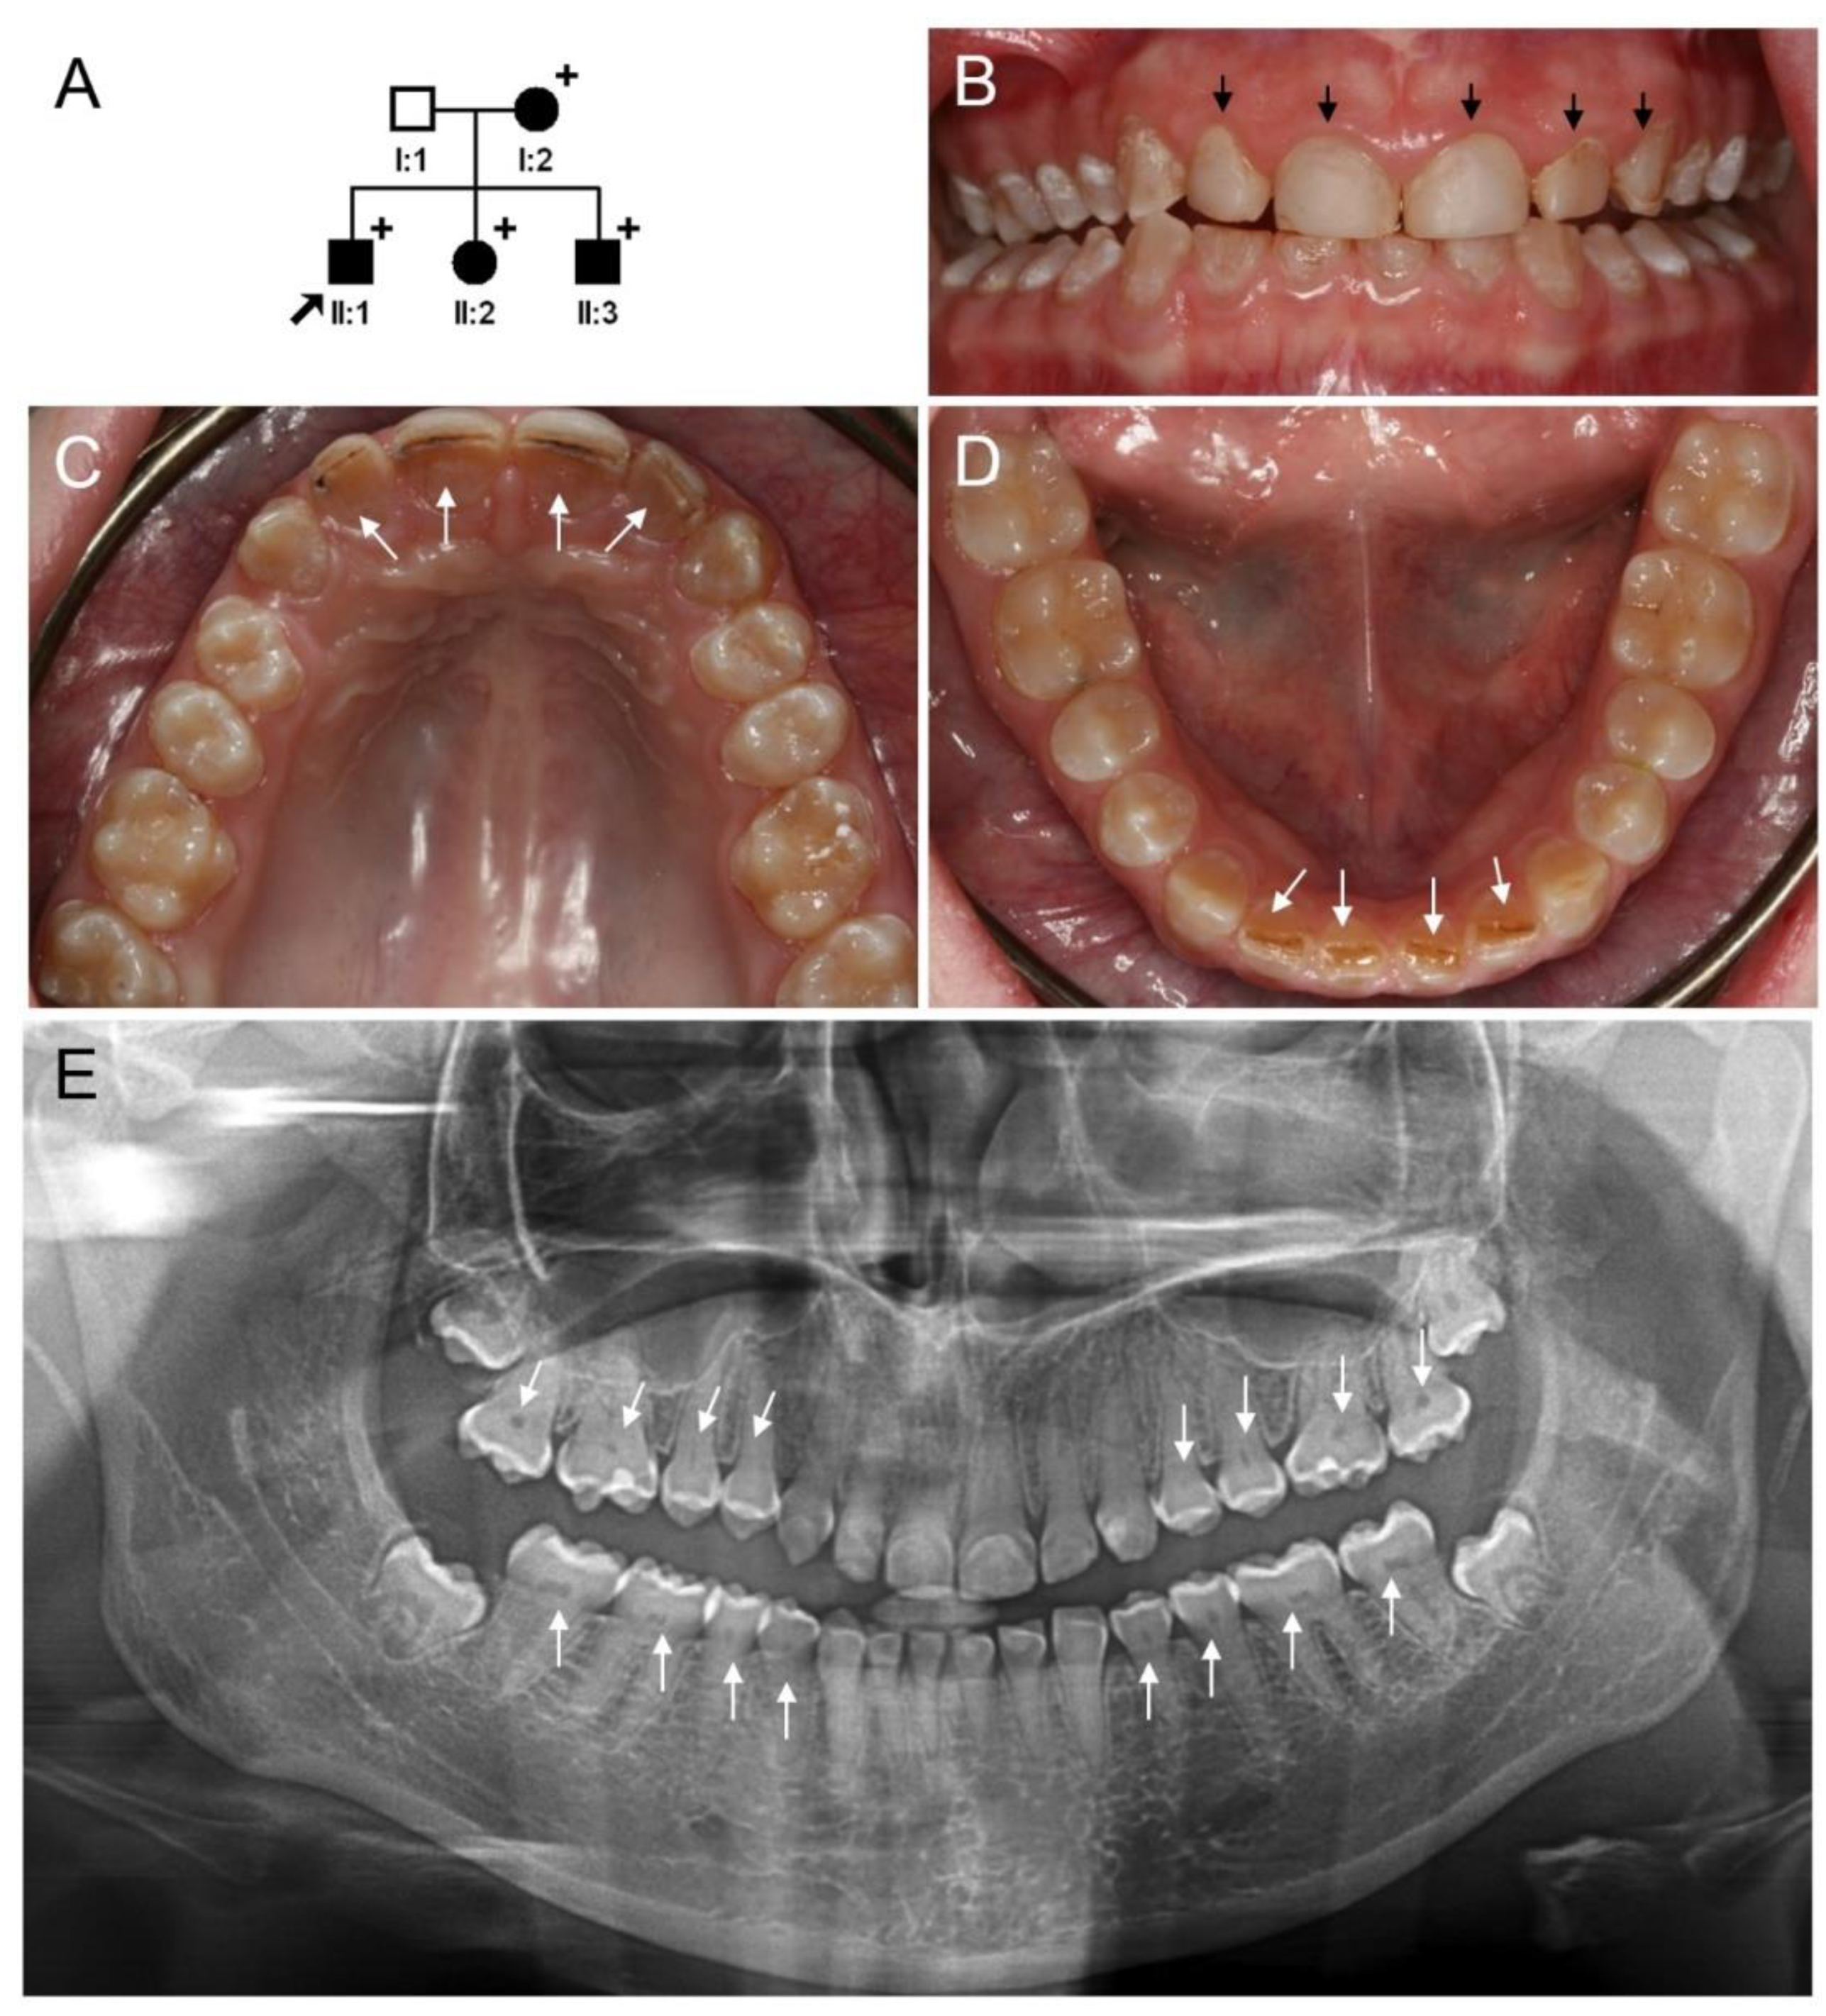

3.1. Clinical Phenotype and Diagnosis of Family 1